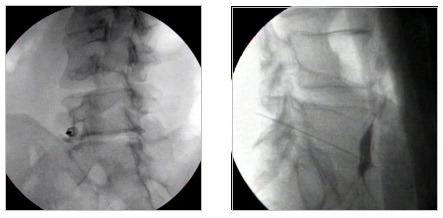

Η εμφύτευση αντλίας γίνεται συνήθως με γενική αναισθησία ή μέθη. H χειρουργική τεχνική περιλαμβάνει την εισαγωγή του καθετήρα έγχυσης στον υπαραχνοειδή χώρο μέσω οσφυονωτιαίας παρακέντησης στο ύψος των κατώτερων οσφυϊκών διαστημάτων, έχοντας τον ασθενή σε πλάγια θέση. Ο καθετήρας προωθείται ακτινοσκοπικά έως το ύψος των κατώτερων θωρακικών διαστημάτων. Στη συνέχεια το άκρο του καθετήρα ενώνεται μέσω ενός συνδετικού καθετήρα με τη γεννήτρια της αντλίας, η οποία εμφυτεύεται υποδορίως στην πλάγια επιφάνεια της κοιλιακής χώρας. Η χορηγούμενη δόση φαρμάκου εξατομικεύεται και τροποποιείται ανάλογα με τις ανάγκες του ασθενούς με την βοήθεια ενός εξωτερικού προγραμματιστή. Η αντλία ανατροφοδοτείται με φάρμακο σε τακτά χρονικά διαστήματα ανάλογα με τις ημερήσιες ανάγκες του ασθενούς. Τα φάρμακα που χρησιμοποιούνται συνήθως για τον έλεγχο του πόνου είναι η μορφίνη, η κλονιδίνη και η ζικονοτίδη.

Πρόκειται για ελάχιστα επεμβατικές θεραπείες, οι οποίες εκτελούνται με διαδερμική προσπέλαση και ενδείκνυνται για τη θεραπεία του πόνου σε ασθενείς με οστεοπορωτικά και παθολογικά κατάγματα των σπονδύλων από μεταστατική καρκινική νόσο. Η κυφοπλαστική αποκαθιστά το ύψος του σπονδύλου με χρήση ειδικού μπαλονιού και εισαγωγή τσιμέντου, ενώ η σπονδυλοπλαστική αφορά σε απλή εισαγωγή τσιμέντου στον καταγματικό σπόνδυλο. Και οι δύο τεχνικές γίνονται μέσω ειδικών trocar που εισάγονται διαδερμικά υπό ακτινοσκοπικό έλεγχο στους αυχένες των σπονδύλων και προωθούνται στο σπονδυλικό σώμα, όπου γίνεται η έγχυση του τσιμέντου ταχείας πήξης. Το τσιμέντο σταθεροποιεί τον σπόνδυλο και αποτρέπει την ανάπτυξη κύφωσης στα πάσχοντα σημεία.